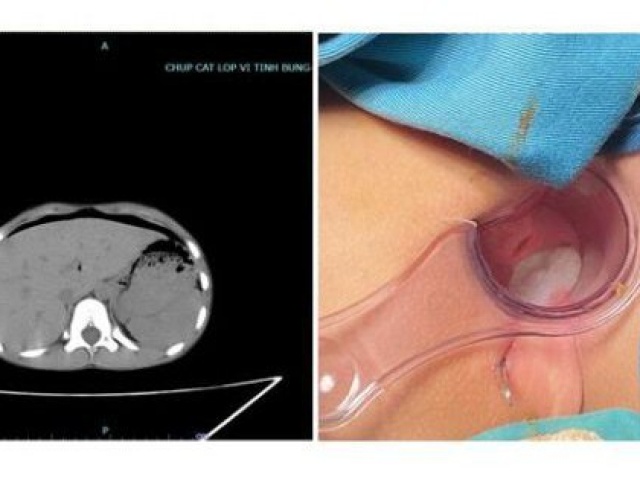

Ăn cá khô ngăn khối u phát triển là thông tin không chính xác. (Ảnh minh họa)